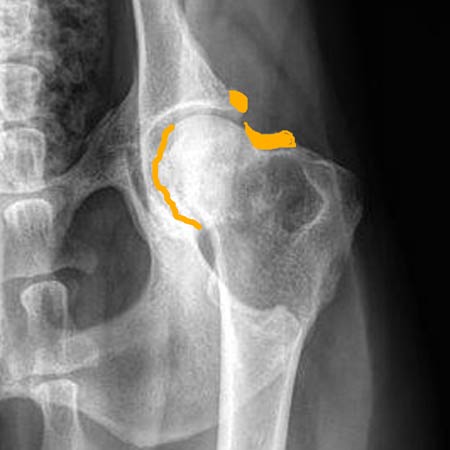

| Uitleg heupfoto's: rechts een uitvergroting van de linkerheup van de linker foto (dit is de slechtste heup). In geel zijn de botwoekeringen aangegeven en de onregelmatige lijn van de heupkop. De kommen zijn diep genoeg, de rechter kop zit mooi diep, de linker iets minder diep. | |